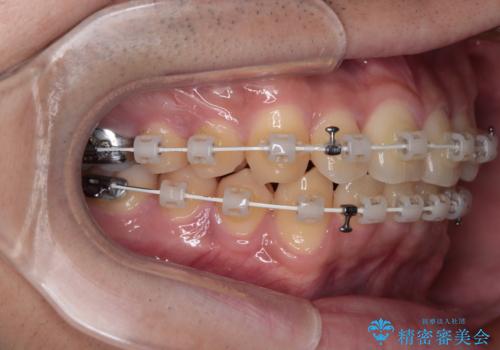

- 矯正装置

- 審美装置

- 上下前歯の捻れやデコボコを気にして来院された患者様です。

マウスピース矯正でもワイヤー矯正でも対応可能でしたが、極力楽をして治したいとのことでワイヤー装置にて治療をおこなうこととしました。

口元はそれほど突出しておらず、患者様自身も気にしていらっしゃいませんでしたが、前歯の捻れやデコボコを解消すると、前方に拡大され、治療後に出っ歯仕上がりとなるリスクがあったため、補助装置により上顎臼歯を後方移動していくこととしました。

昼休みを活用して通院してくださり、1年半であっという間に終えることができました。